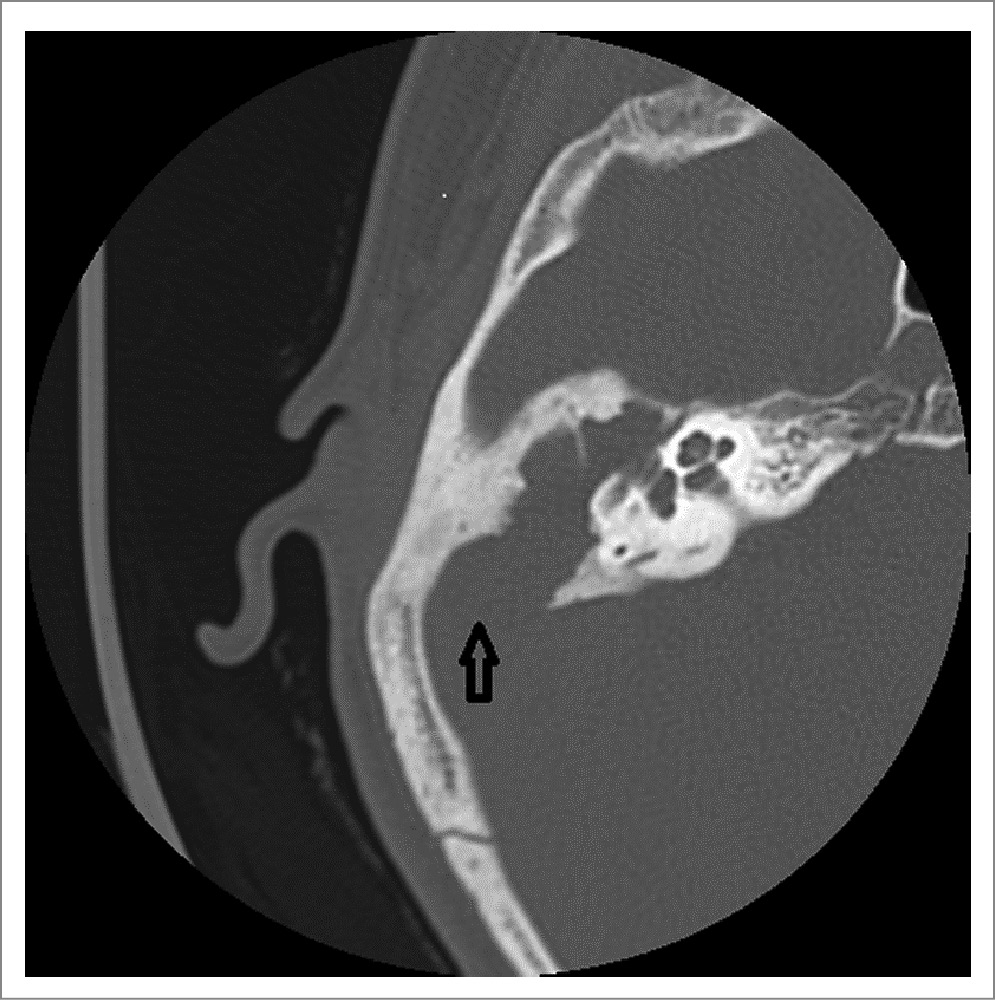

Концепция отохирургии

Имея характер деструктивного роста, холестеатома уха увеличивается в размерах, разрушает слуховые косточки, заполняет ячейки сосцевидного отростка, доходит до мозговых оболочек и капсулы лабиринта, разрушает канал лицевого нерва. Зачастую холестеатома уха достигает размера грецкого ореха и имеет расходящиеся в различных направлениях отростки. Содержащие токсическую жидкость кисты холестеатомы могут являться причиной внутричерепных и септических осложнений (рис. 1).

Рис. 1. Срез спиральной компьютерной томограммы височной кости: на месте аттика и антрума располагается гигантская кариозная полость. Стрелка указывает на значительный дефект пирамиды височной кости, граничащий с задней черепной ямкой.